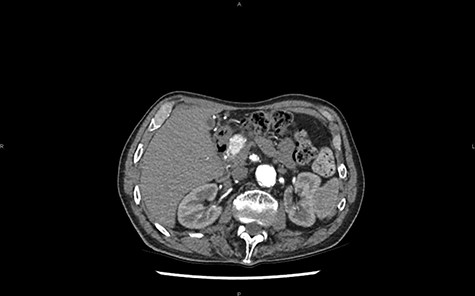

A CT scan later highlights the 25 mm lesion and the dilation of the Wirsung canal (Fig. 1). The contrast enhancement does not support the diagnosis of adenocarcinoma. Considering these features, the differential diagnosis with a neuroendocrine tumor (NET) must be made. No pathological somatostatin receptor fixation is observed during octreoscan.

CT in axial section, arterial phase: visualization of a hypervascular structure at the level of the pancreas head.